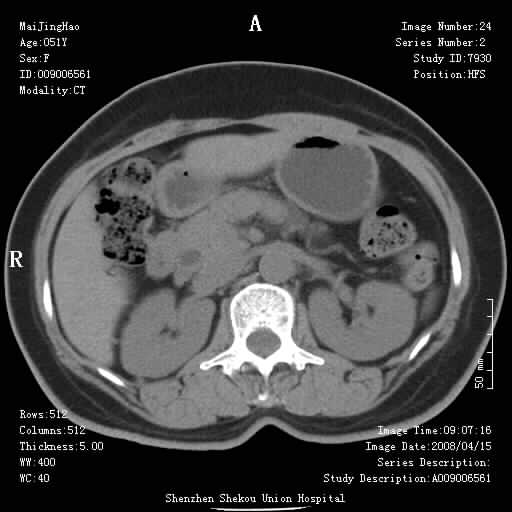

以下是引用听蝉观竹在2008-4-26 14:21:00的发言:[br]这个病例许多人认为“胰头增大”,那么到底胰头增大的标准是什么呢?

以下是引用听蝉观竹在2008-4-27 10:10:00的发言:[br]关于胰头大小问题有几种测量方法和正常值:[br][br]1、直量法:横径<4cm;[br]2、胰头横径与相邻层面椎体横径的比值为二分之一,超过椎体横径就提示胰头增大;[br]3、正常组成年人肠系膜上动、静脉水平夹角正常值范围为4.9°~34.7°大于35°提示胰头增大。[br][br]上述方法只是一种具体的判断,是“量”的评估,更重要的是“质”的评估:一是观察边缘是否光滑,有无局部隆起,有无分叶;二是观察密度(增强,尤其在动脉期和门脉期)是否均匀。[br][br]所以对于胰头是否有异常不仅仅是是目测可以解决问题的,不要轻易就说“胰头增大”。还有一个问题就是测量胰头应该在增强ct上进行,这样可以避免将血管测量进去。[br][br]为什么啰嗦讲怎么多,因为我们实际工作中同样存在影像科医生和临床医生动不动就说胰头增大,说是胰头癌。大家看看是不是这种情况?[br][br] 我个人观点-----本病例的胰头不增大。[br][br][本贴已被 听蝉观竹 于 2008-4-27 10:12:41 修改过]